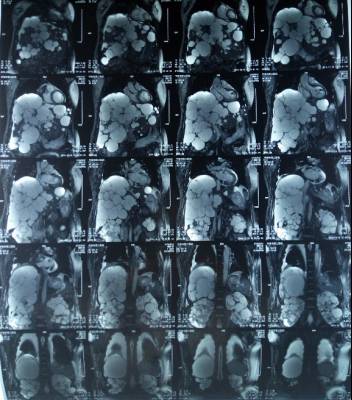

凝血功能及血小板计数均在正常范围内。阅当地医院DSA造影,提示右侧颈内-后交通动脉瘤(图2); 3-D重建后示: 囊性动脉瘤位于右侧颈内动脉-后交通动脉交叉处,前外侧朝向(图3)

图2. 当地医院DSA,前后位示:A:右侧颈内-后交通动脉囊性动脉瘤(箭头所示);左侧颈内动脉系统未见明显异常。